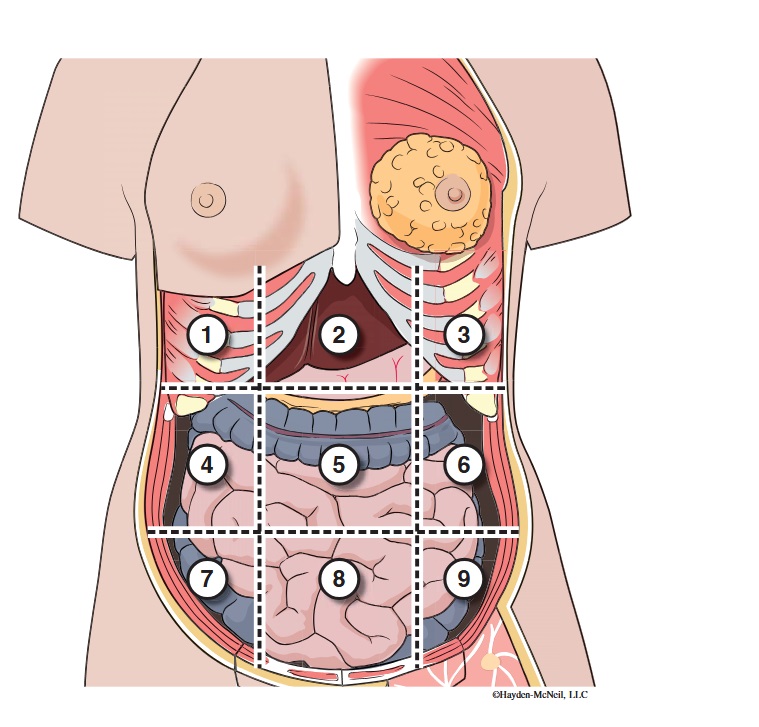

What abdominal region is labeled #1?

right hypochondriac

What abdominal region is labeled #2?

epigastric

What abdominal region is labeled #3?

left hypochondriac

What abdominal region is labeled #4?

right lumbar

What abdominal region is labeled #5?

umbilical

What abdominal region is labeled #6?

left lumbar

What abdominal region is labeled #7?

right iliac/ inguinal

What abdominal region is labeled #8?

hypogastric

What abdominal region is labeled #9?

left illiac/ inguinal

What organs are apart of the right hypochrondriac region?

right lobe of liver, gallbladder, right adrenal gland

What organs are apart of the epigastric region?

pyloric end of stomach, duodenum, pancreas

What organs are apart of the left hypochondriac region?

stomach, spleen, left adrenal gland

What organs are apart of the right lumbar region?

ascending colon, right kidney, portion of small intestine

What organs are apart of the umbilical region?

omentum, mesentery, small intestine

What organs are apart of the left lumbar region?

descending colon, left kidney, portion of the small intestine

What organs are apart of the right iliac/ inguinal region?

cecum of large intestines, appendix, right ovary

What organs are apart of the hypogastric region?

ileum, bladder, uterus

What organs are apart of the left iliac/ inguinal region?

sigmoid colon, left ureter, left ovary